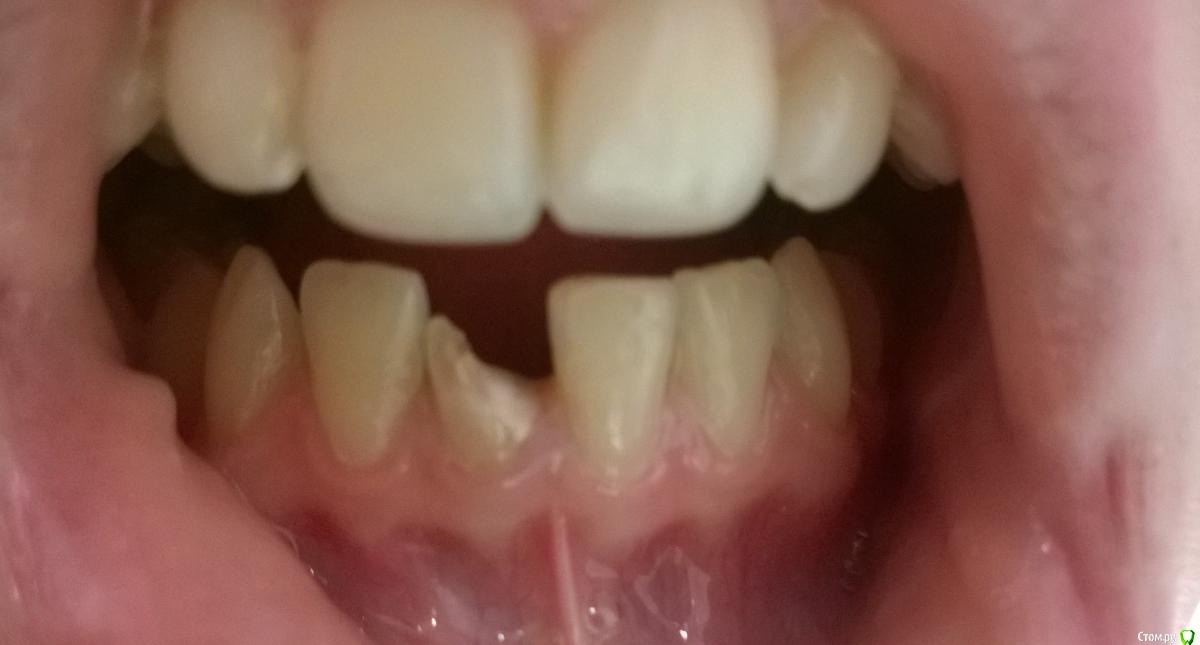

orlova Опубликовано 14 августа, 2016 Поделиться Опубликовано 14 августа, 2016 Доброго времени суток.В результате травмы в 2011г потеряла больше половины 41 зуба(нерв удалён)Обратилась в местную частную стоматологию, там мне заново запломбировали канал и вот сейчас хотят поставить стекловолоконный штифт и безметалл E-max.Но доктора как-то не были уверенны в том, что действительно нужно делать и что выбрать.И ещё один момент: доктор сказал, что у меня слишком маленький корень и из-за этого нужно ставить стекловолоконный штифт, но я читала, что как раз таки наоборот не рекомендуют ставить штифт, если корень зуба маленький.По этой причине пошла в другую стоматологию, где хотят сделать всё совершенно по-другому: не ставить штифт, а поставить вкладку и металлокерамическую коронку (цена больше 25к).Что посоветуете и как прокомментируете план лечения? Я в полнейшей растерянности. Хочется к 1 сентября быть уже с зубом.Спасибо! Ссылка на комментарий

krokomot Опубликовано 14 августа, 2016 Поделиться Опубликовано 14 августа, 2016 Маленький у вас не корень а коронка, точнее что от нее осталось, стекловолоконный штифт и Е-мах хороший вариан, я бы выбрал его, эстетика будет скорее всего лучше чем на металлокерамике, это учитывая что я не знаю уровень технической части предложенных вами стоматологий 1 Ссылка на комментарий

Bier Опубликовано 17 августа, 2016 Поделиться Опубликовано 17 августа, 2016 а нужен ли там вообще штифт? Ссылка на комментарий